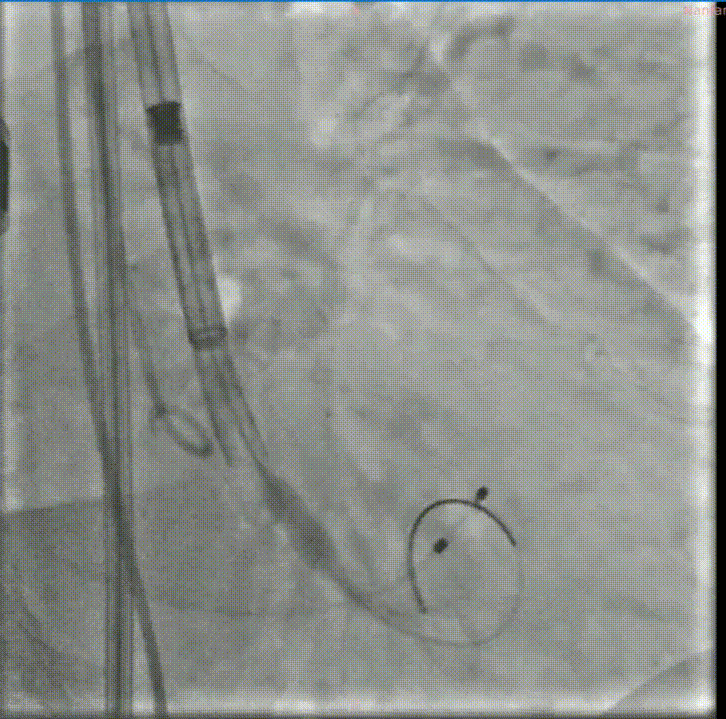

释放初期预释放

释放到50%回收

快速起搏下释放到80%

释放前造影确定位置和深度

完全释放

最后造影

闭合血管入路,完成手术。本例难点在于SAVR术后结构性瓣膜衰败导致主动脉瓣反流,原外科瓣膜未见钙化,术前经充分沟通,确定植入深度于瓣架第一节点与第二节点间,保证瓣架底部在外科瓣膜环上具有足够锚定力。术中,瓣架完全释放前小弯侧深度稍大于大弯侧,微量PVL,在最终时提示术者对递送系统轻微施加推力,释放后两侧深度达到平衡,PVL消失,平均压差2mmHg,舒张压即刻恢复正常。